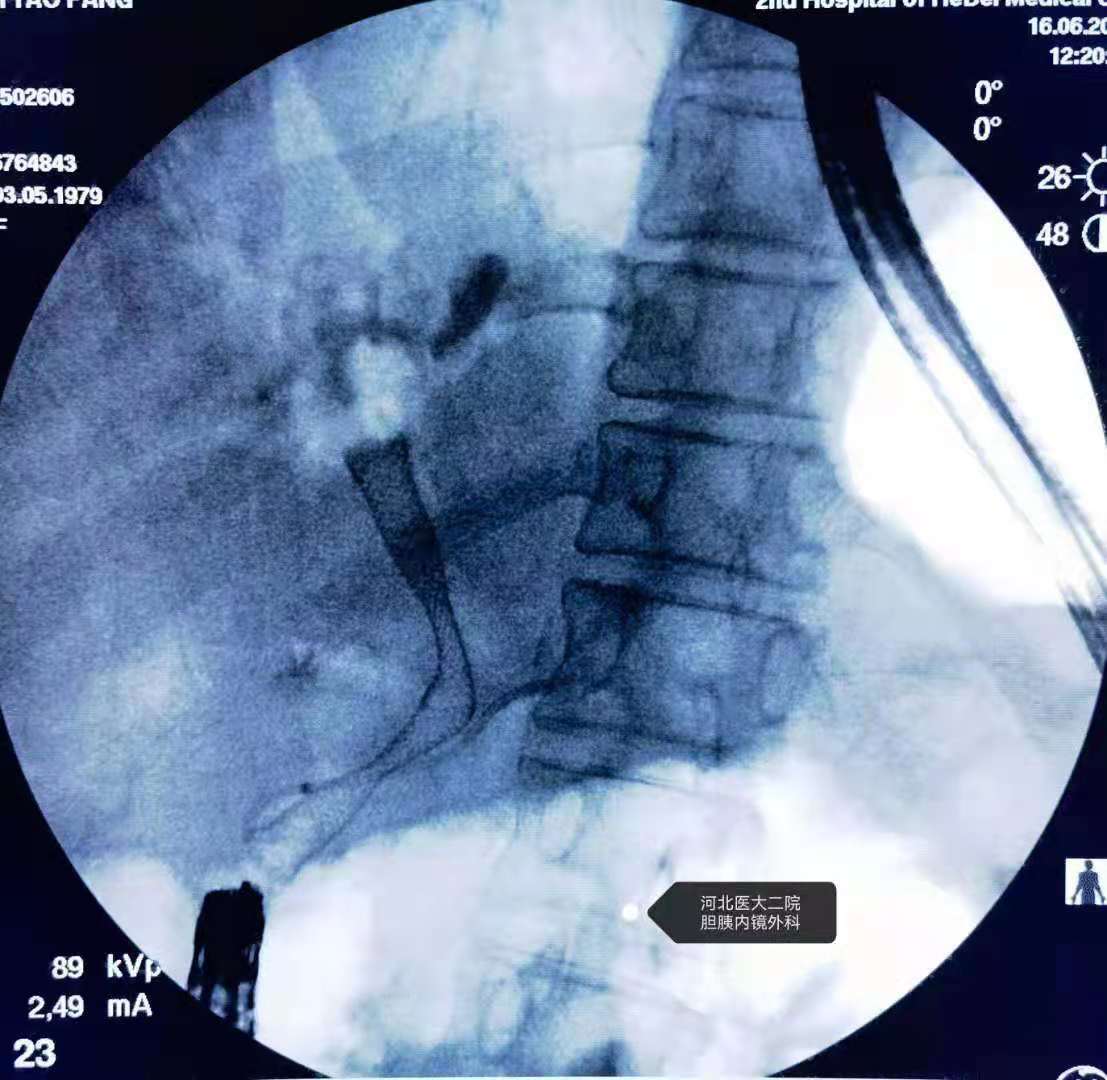

造影。